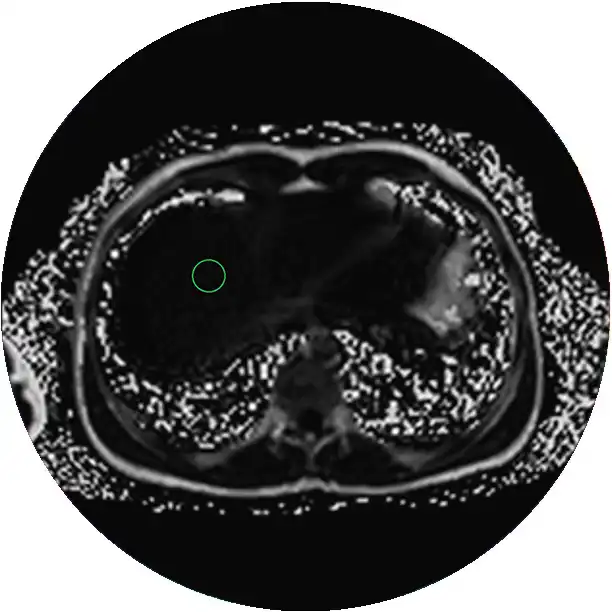

What is MRI Liver w/ Eovist® Contrast?

MRI Liver with Eovist® contrast is the only FDA-approved hepatobiliary-specific contrast agent (HBA) for MR liver imaging. An MRI Liver w/ Eovist may be prescribed by a liver specialist to detect and characterize lesions in patients with known or suspected focal liver disease.

• CPT 74183 MRI Liver w/ Eovist